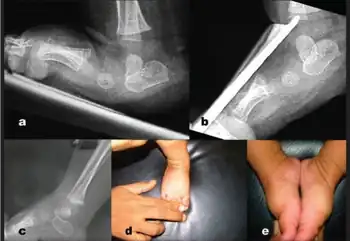

| a) Lateral X-ray right foo with congenital vertical talus shows irreducible talonavicular joint. b) stress plantar flexion view shows fixed plantar flexed talus c) follow up X-ray- reduction of talonavicular joint with the track of k-wire in talar body d,e) photograph showing good correction of foot deformity | |